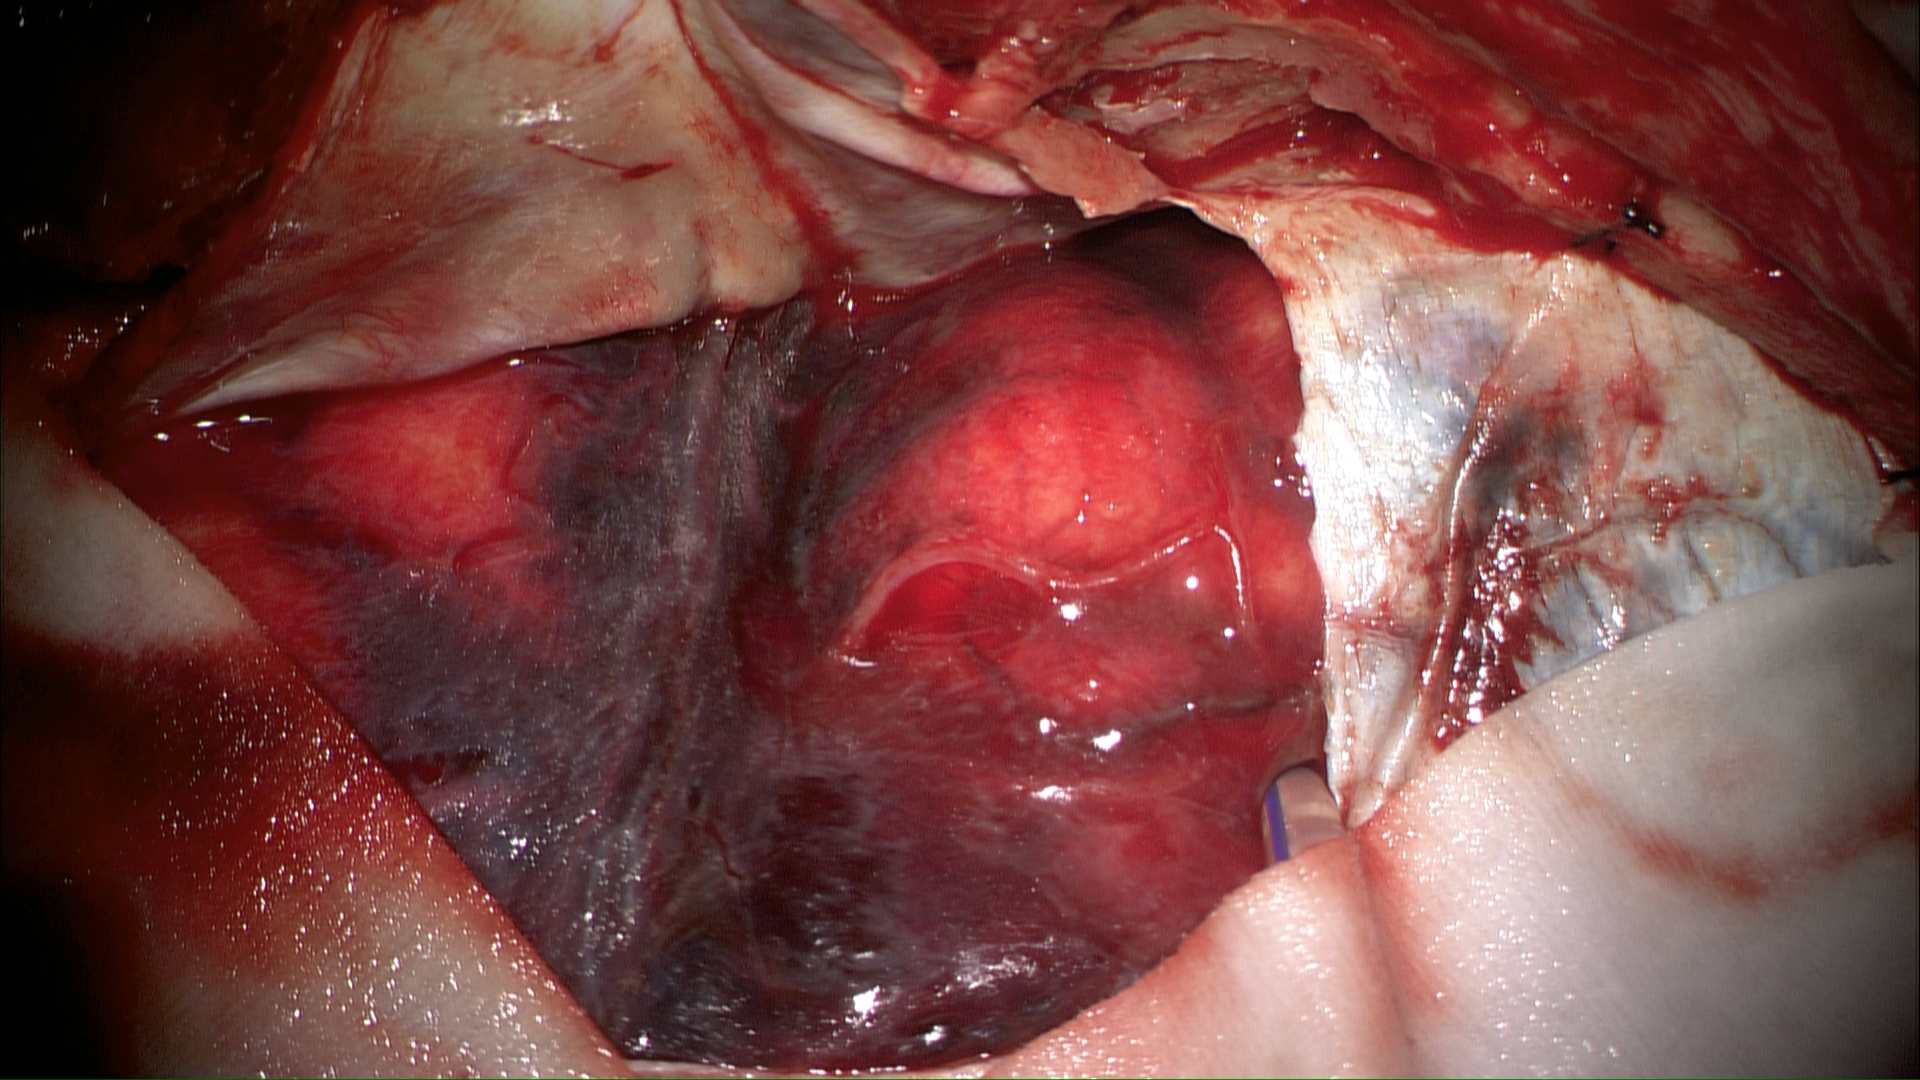

微小动脉瘤1例

患者老年女性,72岁,昏迷入院。